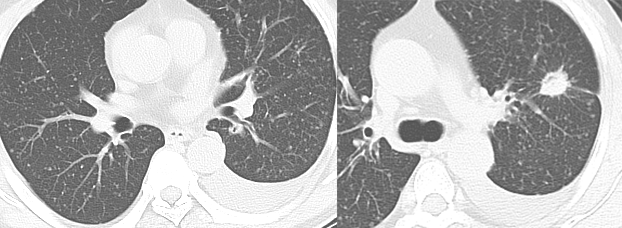

粟粒性转移

粟粒状病灶多见于甲状腺癌、肝癌、胰腺癌及绒毛膜上皮癌转移。常同时伴有纵隔淋巴结肿大及其他脏器转移。

男性,45 岁。左肺上叶肺癌伴双肺粟粒性转移。